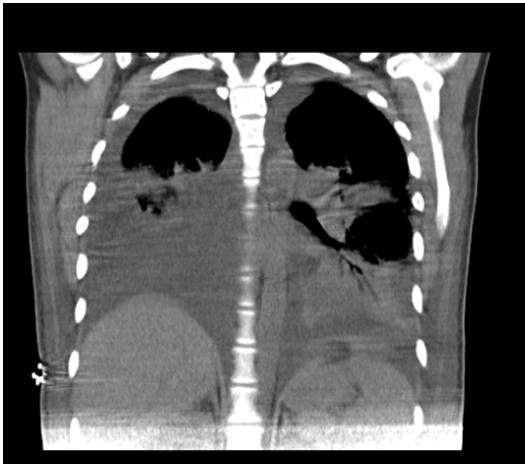

On day 4 of intravenous antibiotic therapy with ertapenem (twelfth day of hospitalization, seventh day in the unit) the patient suddenly became tachypneic with saturations of $88\%$, for which a chest tomography was indicated (figure 2 and figure 3) where It showed a large left pleural effusion, which is why a thoracentesis was indicated, draining $620~\mathrm{cc}$ of clear liquid without infectious characteristics in the bacterial culture cytology reading and a negative fungal test. Patient with immediate improvement after drainage of the pleural effusion; for which she was transferred to a general gynecological hospitalization receiving antibiotic treatment with stable vital signs, afebrile, without loss of fetal well-being evaluated by obstetric ultrasound, who completed antibiotic treatment and proposed adjuvant immunotherapy scheme with immunoglobulin G enriched with IgM and IgA with adequate drug tolerance and favorable clinical course.

Figure 2: Chest tomography, coronal section. Bilateral pleural effusion. Source: authors. Figure 3: Chest tomography, axial slice. Bilateral pleural effusion. Source: authors.